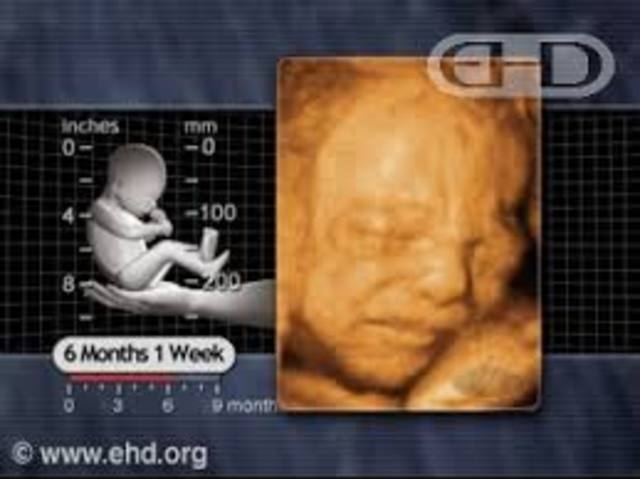

• 6th Month (Week 26-28)

6th Month (Week 26-28)

Week 26 cont-

If you're having a boy testicles are continuing their journey from the pelvis towards the scrotum

Baby's taste buds are now fully developed

Nostrils are beginning to open

Mouth and lips are becoming more sensitive

Week 27-

Same as a head of cauliflower

Opens eyes for first time

Baby experiences Rapid Eye Movement (REM) sleep

Week 28-

Weighs same as an aubergine

Hiccuping is common to feel you baby do in the womb